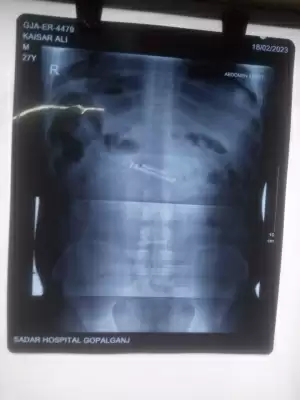

इसी बीच, 18 फरवरी को कैशर के पेट में अचानक दर्द शुरू हो गया। जेल प्रशासन आनन फानन में उसे सदर अस्पताल इलाज के लिए ले गया। जब वहां कैदी के पेट का एक्सरे हुआ तो मामले का खुलासा हुआ। एक्सरे में कैदी के पेट में मोबाइल जैसी कोई वस्तु दिख रही है।

पुलिस के एक अधिकारी ने बताया कि कैदी के पेट के आपरेशन के लिए एक मेडिकल बोर्ड का गठन कर पटना मेडिकल कॉलेज अस्पताल रेफर कर दिया गया है।